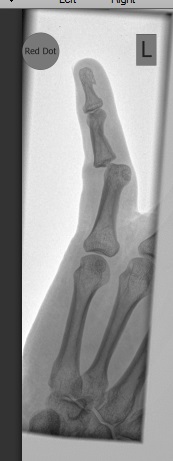

y prior Tom was lead on a rough guide to the course. Dry, slippery in places due to the dust and riding up nice downhills raised a few complaints. Thursday night ran part of the course again with different faces, a slower pace and the lack of fun seemed apparent. Friday was a trundle with Chris Noble in greasy conditions on Michelin Dry 2 tyres. Flick and slip and slide and trouble. Down Coldean some damp roots and a tree produced a bad dislocation. Adding to all the other injured riders this year I could not even claim a speed or bravery badge as compensation.